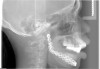

Prior to implant placement, the vertical dimension of occlusion had to be reestablished and a new functional posterior occlusal plane developed. Within this framework, the axial position of the implants could be established. However, the positions of these implants were not solely predetermined by the bony architecture of the newly reconstructed mandible but also could be altered to conform to the proportional harmony of the lower face. To assist in this determination, a left lateral skull film was obtained (Figure 7) and an analysis of facial form, vertical dimension, and incisor position was performed. It was determined that the vertical dimension of the lower face would need to be increased; the posterior occlusal plane would need to be intruded; and the axial position of the lower incisor implants would have to be upright over the newly augmented ridge. In order to establish an esthetic anterior occlusal plane, the upper incisors would have to be retracted without extrusion.9 Final vertical dimension was confirmed by a CBCT scan with a modified surgical guide in place (Figure 8), and this same guide was used for the placement of 10 endosseous dental implants. Then, a transitional lower denture was fabricated and orthodontic treatment was instituted while the implants were allowed to integrate.

Figure 7  Cephalometric x-ray with an analysis of facial form, vertical dimension, and incisor position.

Figure 7